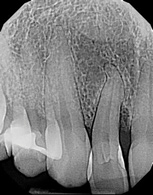

(3.) Surgical photograph of tooth No. 7 exhibiting grooves extending to root, severe bone loss, lack of palatal plate, and excess enamel malformation.

Figure 3

The patient was premedicated with an antibiotic (ie, clindamycin 150 mg; orally, three times daily) and an analgesic (ie, Motrin 800 mg; three times daily, as needed). To enable access to the root and bony defects, two vertical incisions were made on the midpalatal aspects of teeth Nos. 6 and 8 and horizontal incisions were made from tooth No. 6 to tooth No. 8 using a No. 12 scalpel blade (Carbon Steel, Benco Dental). This flap reflection enabled the visualization of significant bone loss and missing palatal plates on tooth No. 7. The magnitude of the gingival groove (ie, length and depth) was also evaluated prior to elimination. Using a fine diamond bur, the large fold of enamel extending to the coronal third of the root was reduced and the deep grooves were eliminated. After the bony defect on the midpalatal and mesial aspect of tooth No. 7 was grafted with particulate freeze-dried bone allograft (Cortical bone, Maxxeus Dental) and covered with a resorbable membrane (Bio-Gide®, Geistlich Pharma North America, Inc.), the flap was closed with PGA sutures (Figure 3 through Figure 5).